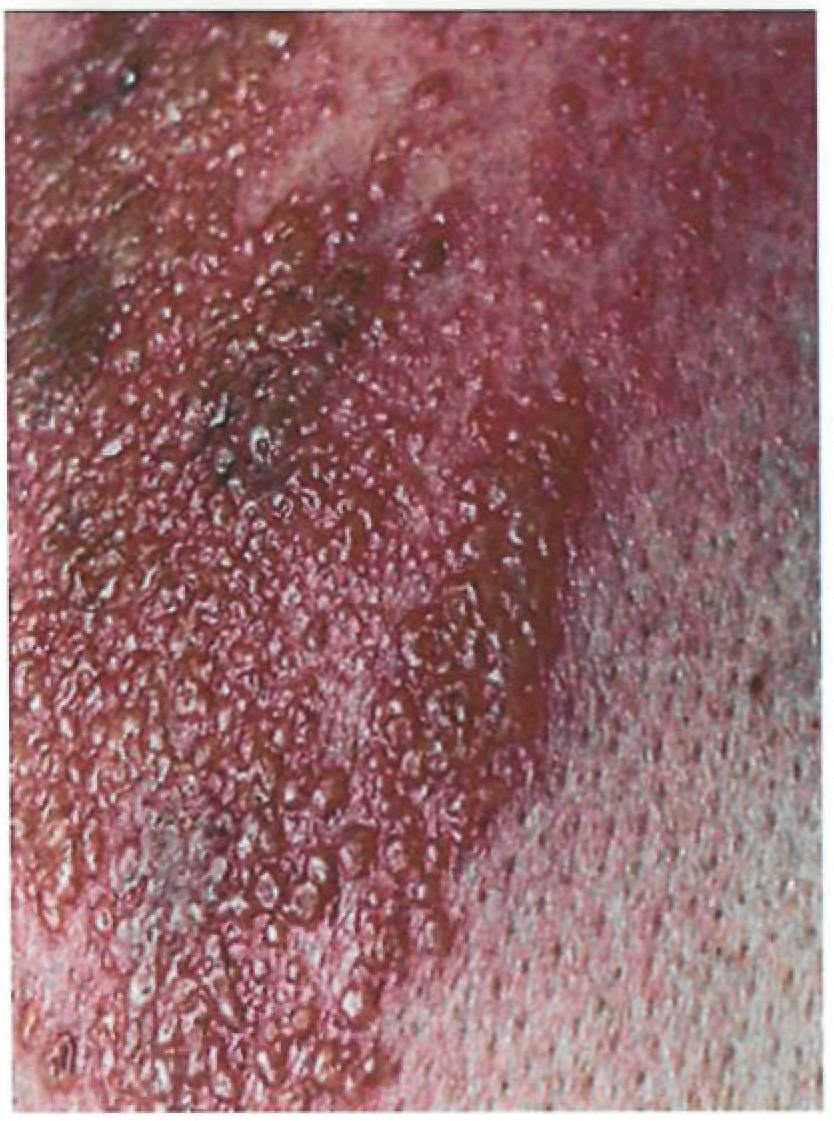

Период высыпаний

На 3-4-й день болезни температура тела снижается до субфебрильной, одновременно на коже головы (прежде всего на лице) и на слизистых оболочках полости рта, гениталий, конъюнктивы, роговицы глаз появляются необильные элементы сыпи. Энантема на слизистых оболочках полости рта обычно предшествует появлению экзантемы. Первые элементы сыпи обычно появляются на лице, быстро распространяясь на верхние конечности, а затем - на туловище и нижние конечности, поражая ладони и подошвы. Распространение экзантемы имеет центробежный характер - на туловище элементов меньше, чем на лице и конечностях.

Высыпания эволюционируют через стадии:

- макула (пятно) (1-2 дня);

- папула (узелок) (1-2 дня);

- везикула (пузырек, заполненный прозрачной жидкостью) (1-2 дня);

- пустула (гнойничок) с пупковидным вдавлением в центре (5-7 дней);

- корочка (7-14 дней).

В 70-80% случаев сыпь характеризуется мономорфностью, в остальных случаях может отмечаться полиморфизм [38]. На одном участке кожи сыпь всегда мономорфна.

В 95% случаев сыпь поражает лицо, в 75% - ладони и подошвы, что является отличительным признаком заболевания. Также поражаются слизистые оболочки полости рта (в 70% случаев), половые органы (30%), конъюнктива и/или роговица (20%). У части пациентов имеет место проктит с поражениями перианальной области изолированно или в сочетании с высыпаниями в области гениталий [39]. Количество элементов сыпи варьирует от единичных до нескольких тысяч [13].